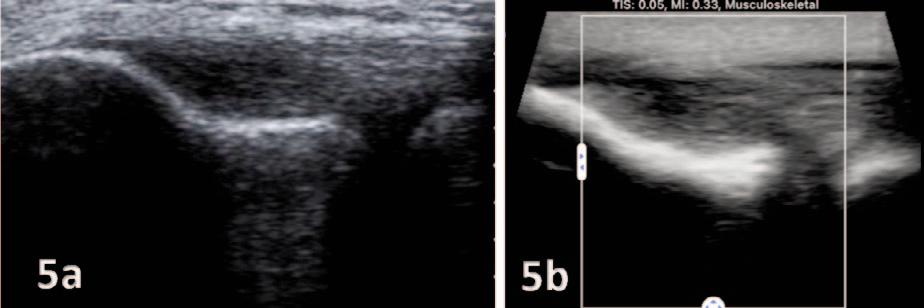

135 Diagnostic Musculoskeletal Ultrasound for the Evaluation of the Lateral Elbow: Implications for Rehabilitation Providers.

Manske RC, Wolfe C, Page P, Voight M.